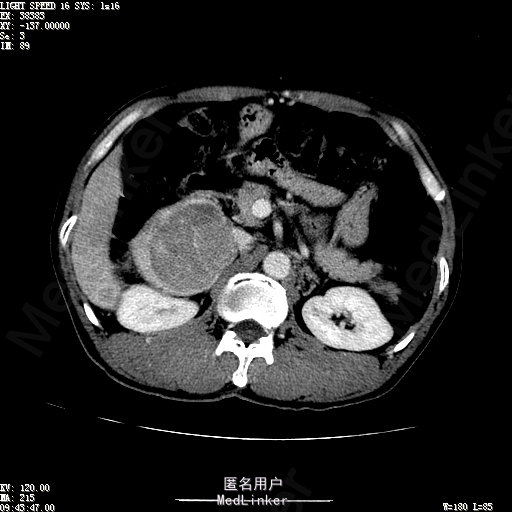

查体:体温36.4℃,脉搏76次/分,呼吸18次/分,血压110/70mmHg。神志清晰,发育正常,营养中等,体位自如,表情安静,慢性病容,检查合作。皮肤粘膜颜色正常,无瘀点、紫癜,有肝掌,无蜘蛛痣,无水肿,毛发的生长与分布正常。浅表淋巴结浅表淋巴结未触及肿大。无巩膜黄染,结膜正常。口唇红润,粘膜正常,舌正常,牙龈正常,扁桃体无肿大,无咽部充血。颈部外形对称,颈静脉正常,肝颈静脉回流征阴性,气管居中。甲状腺正常,无颈部血管杂音。胸部形态正常,呼吸运动平稳规律,无呼吸困难,肋间隙正常。触诊语颤正常,无胸膜摩擦感,肺下界位于右锁骨中线第六肋间。呼吸音正常,未闻及干湿啰音,无胸膜摩擦音。无心前区隆起,心尖搏动正常,心率:76次/分,心律齐,心音正常,无杂音,无心包摩擦音。无大动脉及周围血管征,无奇脉及交替脉,无水冲脉,无枪击音,腹型对称,无腹壁静脉曲张,未见胃肠型及蠕动波,无瘢痕,脐部正常。无压痛,无反跳痛,无腹肌紧张,无腹部包块。肝未触及,Murphy征阴性,脾未触及,肾未触及,无移动性浊音。无肝区叩击痛,无肾区叩击痛,无脾区叩击痛。肠鸣音正常4次/分,无气过水声。外阴及肛门:未查。四肢正常,关节正常,无下肢水肿,无下肢静脉曲张,无杵状指趾。 辅助检查:彩超:肝表面欠光滑,肝内占位5.2*5厘米 ct如下图

诊断:乙肝肝硬化 代偿期 原发性肝癌。 患者病史明确,目前化验转氨酶轻度升高,说明有活动性肝损伤,白蛋白降低提示肝脏合成代谢功能下降,AFP从一年前至今逐渐升高,提示活性肿瘤细胞增多。CT所见明确诊断肝癌,并有周围卫星灶,应近期行TACE治疗。 处置:DSA下肝动脉造影及TACE 手术简要经过:患者平卧位,术区皮肤消毒,铺手术巾,2%利多卡因局麻后,Seldinger法穿刺右股动脉,入血管鞘,5F猪尾管腹主动脉造影,超滑导丝yidao5F RH管腹腔干、肠系膜上动脉、左肾动脉分别造影,腹腔干造影时,见肝右叶7-8处小结节样肿瘤染色,未见外凸生长较大病灶染色。微导管超选肝右动脉注入三氧化二砷碘油混悬液10毫升,横结肠遮挡部位见较大病灶有伞状碘油沉积。复查造影未在见肿瘤染色,拔出导管和血管鞘,穿刺处压迫止血,加压包扎。术毕。

患者术后8天来,无不适,无发热,无腹痛和腹胀,无恶心呕吐,食欲睡眠好,尿便正常。 查体:神志清,巩膜无黄染,心肺听诊无异常,腹软,无压痛,肝脾肋下未触及,移动性浊音阴性,双下肢无浮肿。 复查化验结果:丙氨酸氨基转移酶 116 U/L、天门冬氨酸氨基转移酶 41 U/L、胆碱酯酶 1995 U/L↓、总蛋白 56.3 g/L、白蛋白 25.9 g/L。白细胞计数 5.8 10^9/L、红细胞计数 3.18 10^12/L、血小板计数 175.0 10^9/L、*血红蛋白 83 g/L、血小板分布宽度 15.7 、血小板压积 0.175 %、*红细胞压积 24.6 %、平均红细胞血红蛋白 26.1 pg、平均红细胞血红蛋白浓度 337.0 g/L、平均红细胞体积 77.5 fL、平均血小板体积 10.0 fL、嗜碱性粒细胞百分比 0.4 %、嗜碱性粒细胞数量 0.02 10^9/L、中性粒细胞百分比 70.4 %、中性粒细胞数量 4.10 10^9/L、嗜酸性粒细百分比 2.1 %、嗜酸性粒细胞数量 0.12 10^9/L、单核细胞百分比 12.2 %、单核细胞计数 0.7 10^9/L、淋巴细胞数量百分比 14.9 %、淋巴细胞计数 0.9 10^9/L。甲胎蛋白 23564.00 ng/mL 患者术后第8天开始行FOLFOX6化疗。CT上可见明显碘油沉积,术后甲胎蛋白下降治疗有效。嘱患者术后必须定期复查